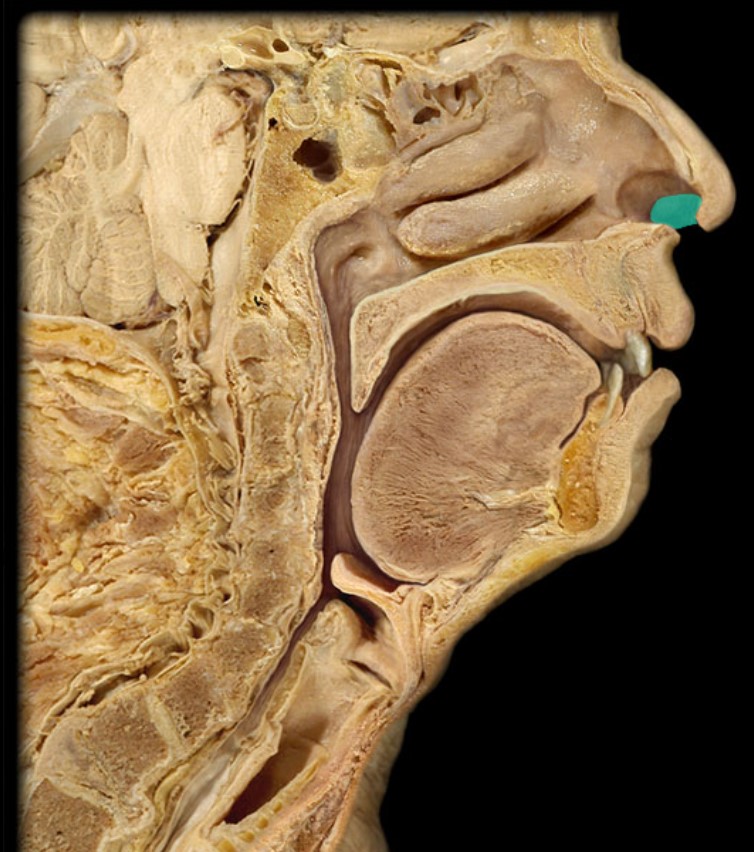

Anatomy 5 - Bifurcated Skull

Thyroid Gland

Atlas

Vertebral Artery

Nasal Septum

Esophagus

Trachea

Vocal Fold

Epiglottis

Hyoid

Mandible

Mylohyoid

Geniohyoid

Genioglossus

Lingual Tonsil

Palatine Tonsil

Uvula

Soft Palate

Palatine Bone

Maxilla

Pharyngeal Tonsil

Auditory Hiatus

Torus Tubarius

Sphenoid Sinus

Inferior Nasal Concha

Middle Nasal Concha

Superior Nasal Concha

Nasal Vestibule

External Nares

Frontal Sinus